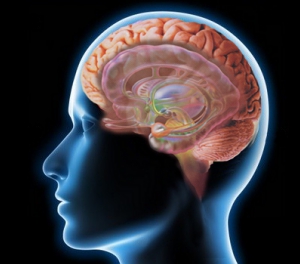

大脳半球は、右脳と左脳の二つが脳梁(のうりょう)と呼ばれる神経線維によって繋がっています。

大脳半球の表面は、4つの葉(よう)に分かれた皮質によって覆われ、表面からは見えない重要な器官もその内側にあります。

ご存知のように脳の表面は、溝(こう)と回(かい)と呼ばれる凹凸があり、それらによって広い表面積を作り出しています。

大脳皮質は脳の表面を取り巻く神経細胞と神経線維でできていて、はっきりと色の違いがあります。

脳の皮質表面は半透明の薄い肌色に似たピンク色をしています。(生きている脳の場合)

その表面からわずか1.5~4.5mm程が脳神経細胞の場所で、一般には灰白色と表現されます。それより深い部分は神経線維です。神経線維の部分は、脂肪で包まれているために白い色をしています。白色と表現されます。

Ⅱ・・・大脳辺縁系 (だいのうへんえんけい)

大脳辺縁系は大脳半球の中の中心部分の臓器です。人の喜怒哀楽などを作り出している重要な領域です。皮質の内側の一部も含まれ内に接しています。これらの部分は、核(かく)と呼ばれる神経細胞の集まった領域です。大脳皮質(表面)の神経細胞とは神経線維で繋がっています。

大脳辺縁系は、扁桃体、海馬、帯状回、脳弓、乳頭体、中隔などで構成されます。

Ⅲ・・・大脳基底核、脳幹 (だいのうきていかく、のうかん)

大脳基底核、脳幹は脊髄の上の部分に位置した脳です。詳しくは![]()

大脳基底核は、尾状核、被殻、淡蒼球、黒質、視床下核などで構成されます。